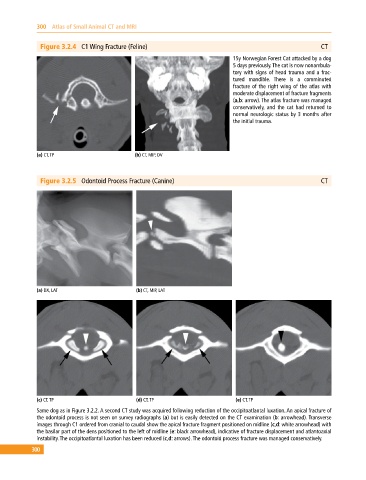

Figure 3.2.4 C1 Wing Fracture (Feline) CT

15y Norwegian Forest Cat attacked by a dog

5 days previously. The cat is now nonambula-

tory with signs of head trauma and a frac-

tured mandible. There is a comminuted

fracture of the right wing of the atlas with

moderate displacement of fracture fragments

(a,b: arrow). The atlas fracture was managed

conservatively, and the cat had returned to

normal neurologic status by 3 months after

the initial trauma.

Figure 3.2.5 Odontoid Process Fracture (Canine) CT

Same dog as in Figure 3.2.2. A second CT study was acquired following reduction of the occipitoatlantal luxation. An apical fracture of

the odontoid process is not seen on survey radiographs (a) but is easily detected on the CT examination (b: arrowhead). Transverse

images through C1 ordered from cranial to caudal show the apical fracture fragment positioned on midline (c,d: white arrowhead) with

the basilar part of the dens positioned to the left of midline (e: black arrowhead), indicative of fracture displacement and atlantoaxial

instability. The occipitoatlantal luxation has been reduced (c,d: arrows). The odontoid process fracture was managed conservatively.